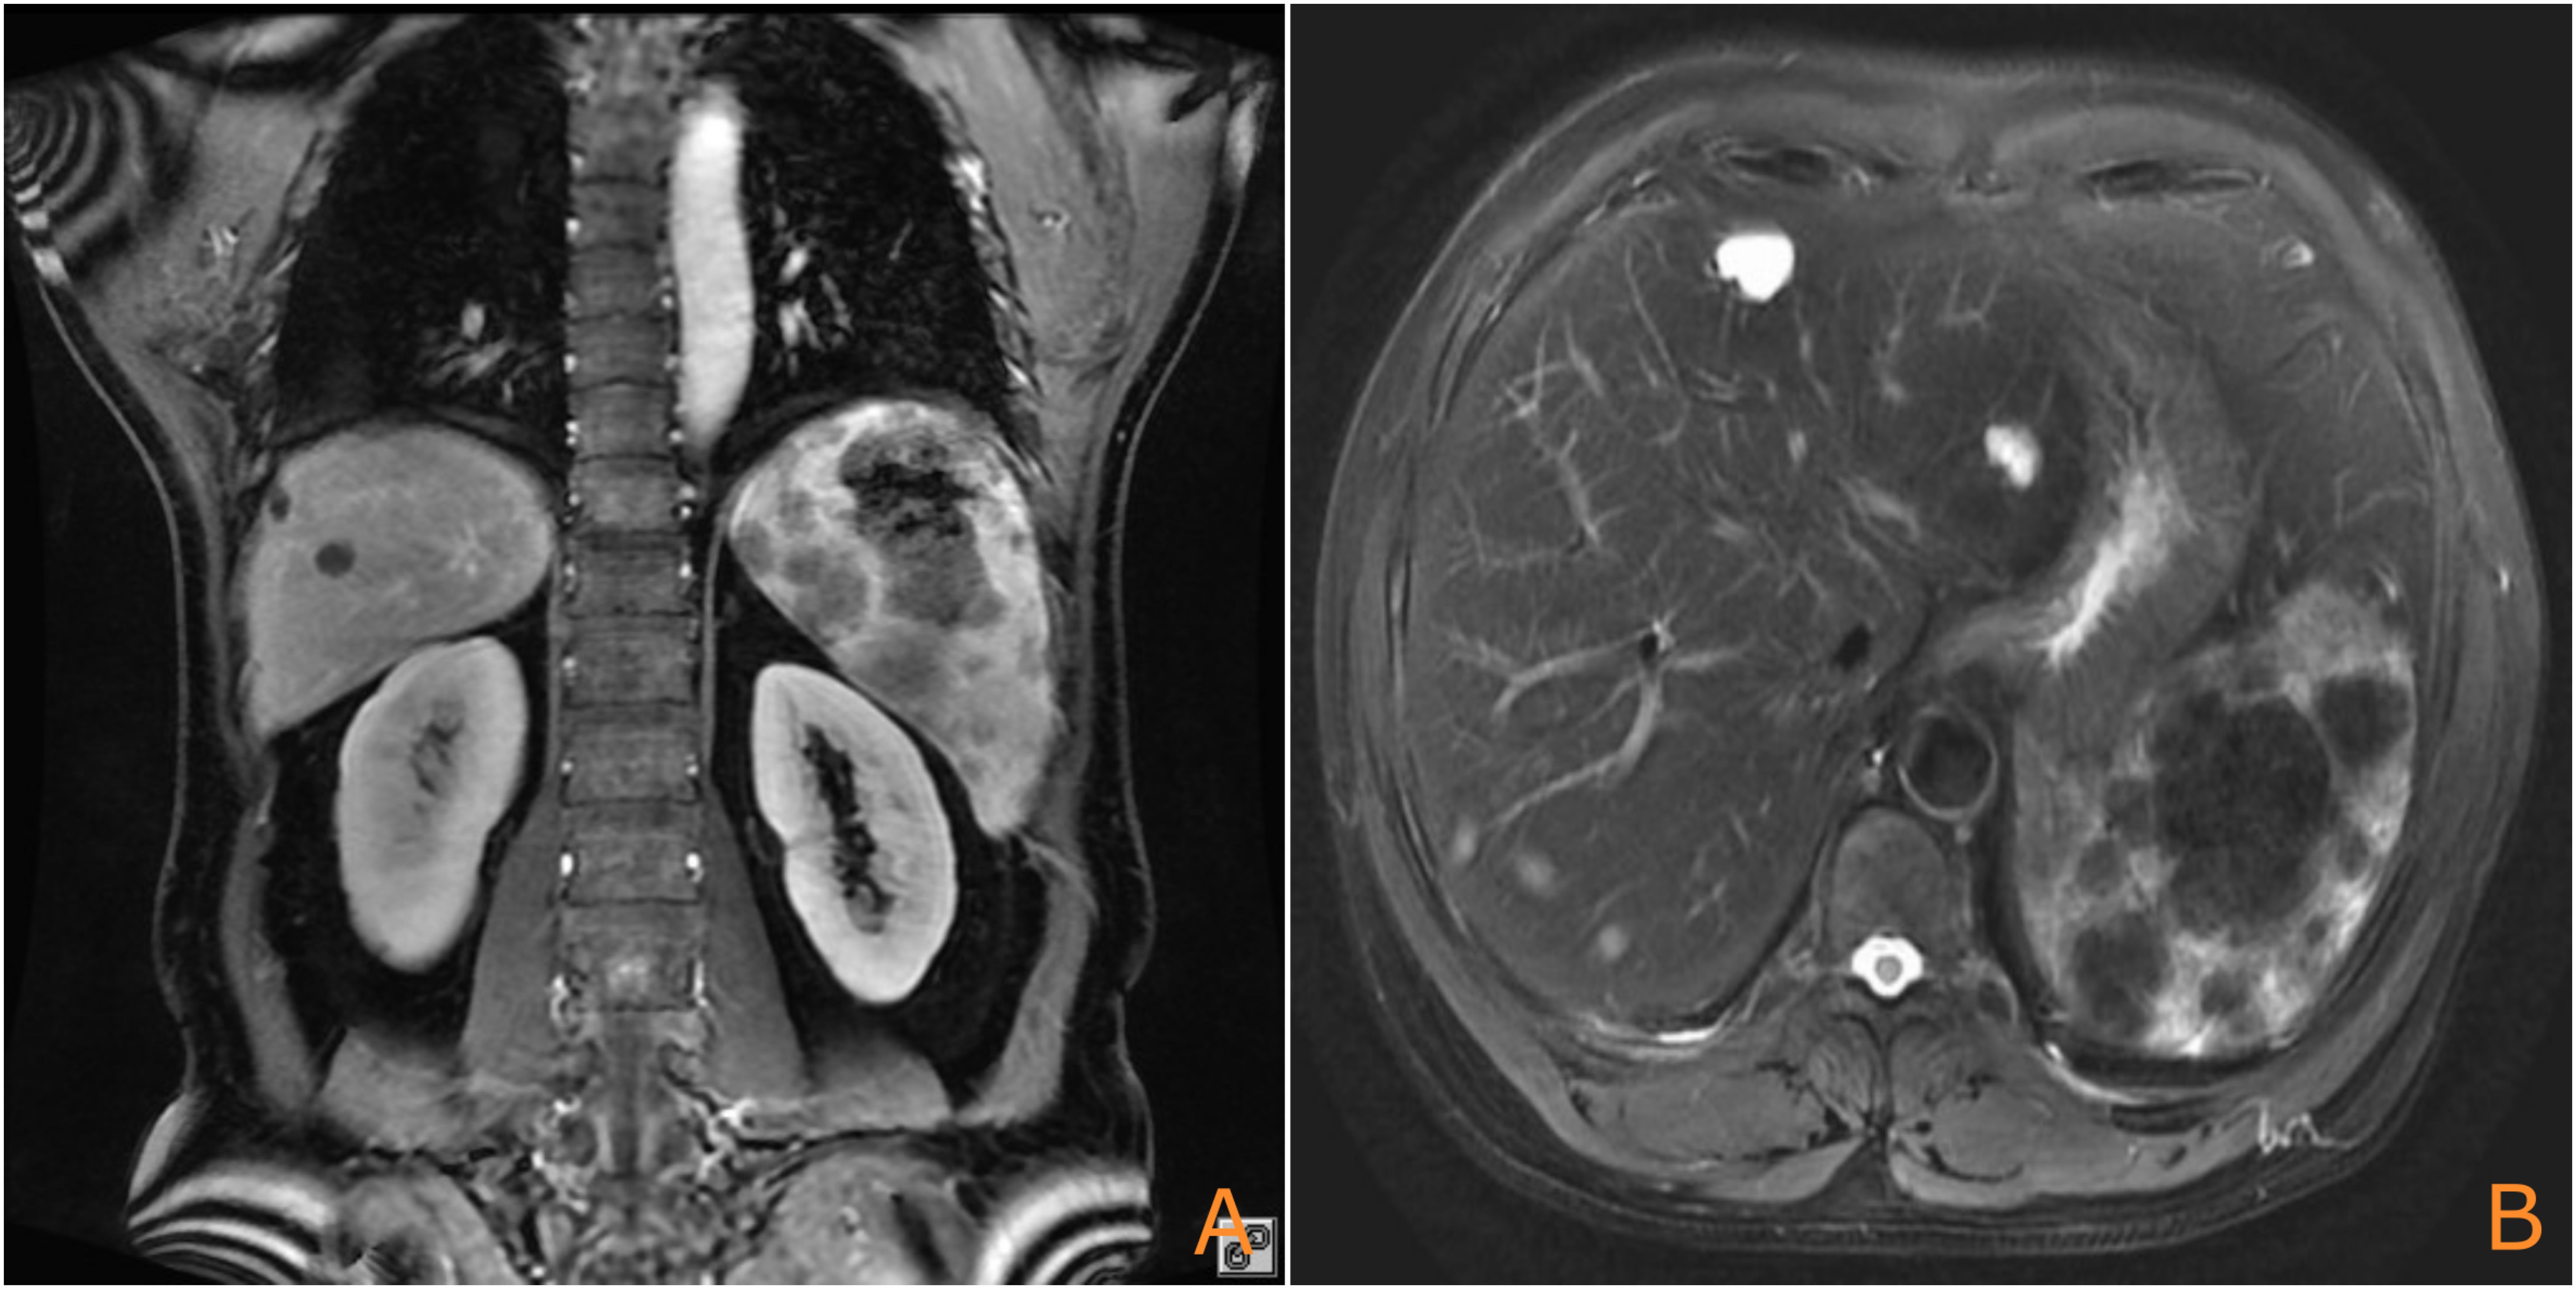

Background Primary splenic angiosarcoma (PSA) is an exceedingly rare and aggressive malignancy with a poor prognosis. This report aims to present a rare case of PSA that progressed to fatal hepatic rupture due to rapid metastatic spread following splenectomy and adjuvant therapy, a review of the relevant literature is also provided to discuss the diagnostic and therapeutic challenges associated with this condition. Case Presentation A 52-year-old male patient presented with acute abdominal pain and hypovolemic shock. Imaging revealed splenic rupture with hemoperitoneum. An emergency splenectomy was performed, and histopathological examination confirmed the diagnosis of angiosarcoma. The patient received postoperative chemotherapy (liposomal paclitaxel) and subsequent targeted therapy (sunitinib). However, rapid hepatic metastasis occurred, leading to spontaneous hepatic rupture and death six months after the initial diagnosis. Conclusion The condition poses a diagnostic and therapeutic challenge due to its nonspecific presentation and high aggressiveness. Early splenectomy remains the prevailing standard of care. This case demonstrates the potential inefficacy of sunitinib against PSA derived hepatic metastases and emphasizes the critical importance of early diagnosis and intervention before splenic rupture occurs. The potential for combination therapies, including immunotherapy, to represent future investigative avenues is a promising area for future research.